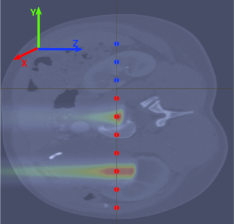

We used the Geant4-based simulation framework GATE (Jan et al., 2011; Grevillot et al., 2011) to generate Monte Carlo simulation data for a proton therapy setup using a mono-energetic proton beam and spread out Bragg peak (SOBP) situation separately. Irradiation of a pencil beam source on an abdominal CT phantom was used for data generation. The phantom dimensions are 302 mm×\times302 mm×\times180.5 mm with the spatial resolution of 0.589 mm×\times0.589 mm×\times 0.500 mm. The HU range of the phantom was divided into 24 bins according to the scheme described in (Schneider et al., 2000), and the details are summarized in Table 1. The beam propagates along the z𝑧z axis, and the beam profile was assumed to be a Gaussian distribution with standard deviations σxsubscript𝜎𝑥\sigma_{x} and σysubscript𝜎𝑦\sigma_{y} in the iso-center position. For mono-energetic proton beam, we have performed 900 simulations for five different spot sizes with standard deviations ranging from 3 to 5 mm with an interval of 0.5 mm in both x𝑥x and y𝑦y dimensions. A total of 150 million protons were used as primary particles having a Gaussian energy spectrum with a standard deviation of 1% from the target proton energy. The simulations were performed for 10 different positions on the CT phantom along the y𝑦y axis with a mono-energetic proton beam with energies ranging from 50 to 122 MeV in 4 MeV intervals. Each irradiation position is spatially 2 cm apart from the other. A visual description of the irradiation configuration on the DICOM phantom is shown in Fig. 1. The distance between the beam nozzle and the face of the phantom is kept 50 cm. The physics list QSP_BIC_HP_EMZ was employed in our study as it showed more accurate results over QSP_BIC_HP_EMY (Winterhalter et al., 2020). 10C, 11C, 13N, and 15O have large production cross-sections. Among them, 11C and 15O have relatively long lifetimes and larger production cross-sections, which are therefore the focus of our study. The depth dose distribution and the production information of positron-emitting isotopes 11C and 15O were stored in a voxelized image using the dose and production-stopping actor available in GATE. Dose and positron activity have been stored with a spatial resolution of 0.589 mm×\times0.352 mm×\times0.205 mm.

For SOBP simulations, a dataset consists of 360 cases with the SOBP of approximately one-quarter of the total range R0 and the maximum beam energy E0 simulated using weighted superposition of mono-energetic proton beams. We selected 12 maximum energies E0s, ranging from 70 to 118 MeV with an energy gap of 4 MeV and irradiated at 10 positions, as shown in Fig. 1. Three spot sizes with standard deviations varying from 3 to 4 mm and an interval of 0.5 mm in both x𝑥x and y𝑦y dimensions were used. Each energy E0 is divided into 15 weighted fractional energies due to a constraint on computing resources. The simulation scheme and weights required for various initial energies are calculated using the analytical framework described in Bortfeld & Schlegel (1996); Jette & Chen (2011).

Figure 1: (a) The simulation setup for the irradiation of the proton beam with the mono-energetic beam and the SOBP case, where the dose of the mono-energetic case is shown in the middle while the dose of the SOBP case is in the lower middle, and the red positions represent the training positions, whereas the blue positions are used for testing. (b) The detector configuration in which the zero position of the detector z𝑧z-axis is aligned with the beam entry face of the phantom, and the detector is translated along the y𝑦y-axis at each position so that the beam is always centered on the detector.